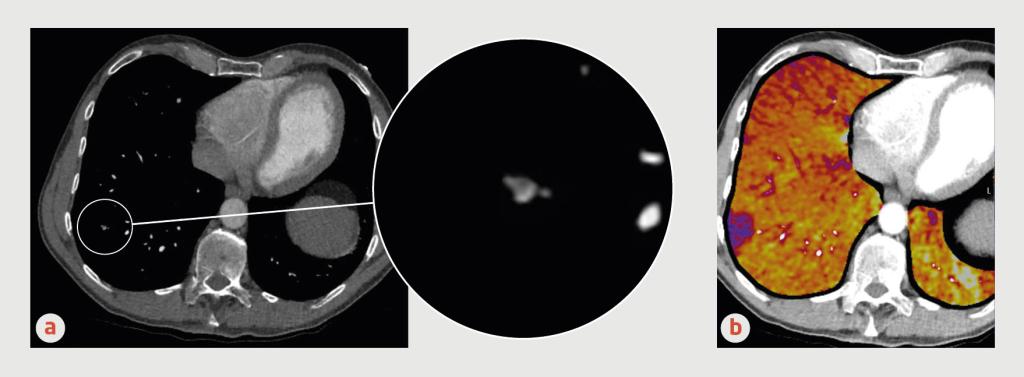

Figuur 1

Geïsoleerde subsegmentele longembolie

Figuur 1 | Geïsoleerde subsegmentele longembolie

CT-angiografie (transversale coupes) van een 57-jarige man, (a) CT met contrast en (b) subtractie-CT met jodium-mapping. Op de uitvergroting van de beelduitsnede in figuur a is een contrastuitsparing te zien in een aftakking van de rechter A. pulmonalis. De subtractie-CT-scan laat een perfusiedefect zien in het verzorgingsgebied van deze aftakking (paars). De conclusie luidt dat het hier gaat om een subsegmentele longembolie.

Met het voortschrijden van de CT-techniek zien radiologen steeds vaker subsegmentele longembolieën. Die naam is ontleend aan de anatomie van de longarteriën. De A. pulmonalis vertakt zich in twee hoofdarteriën (linker en rechter), die zich opsplitsen in lobaire arteriën. Uit de lobaire arteriën ontspringen de segmentele arteriën die de anatomie van de bronchiën volgen. De aftakkingen van de segmentele arteriën zijn de subsegmentele arteriën, waarvan de anatomie interindividuele verschillen kent. Bij subsegmentele longembolie bevindt de trombus zich in een subsegmentele arterie (zie figuur 1).